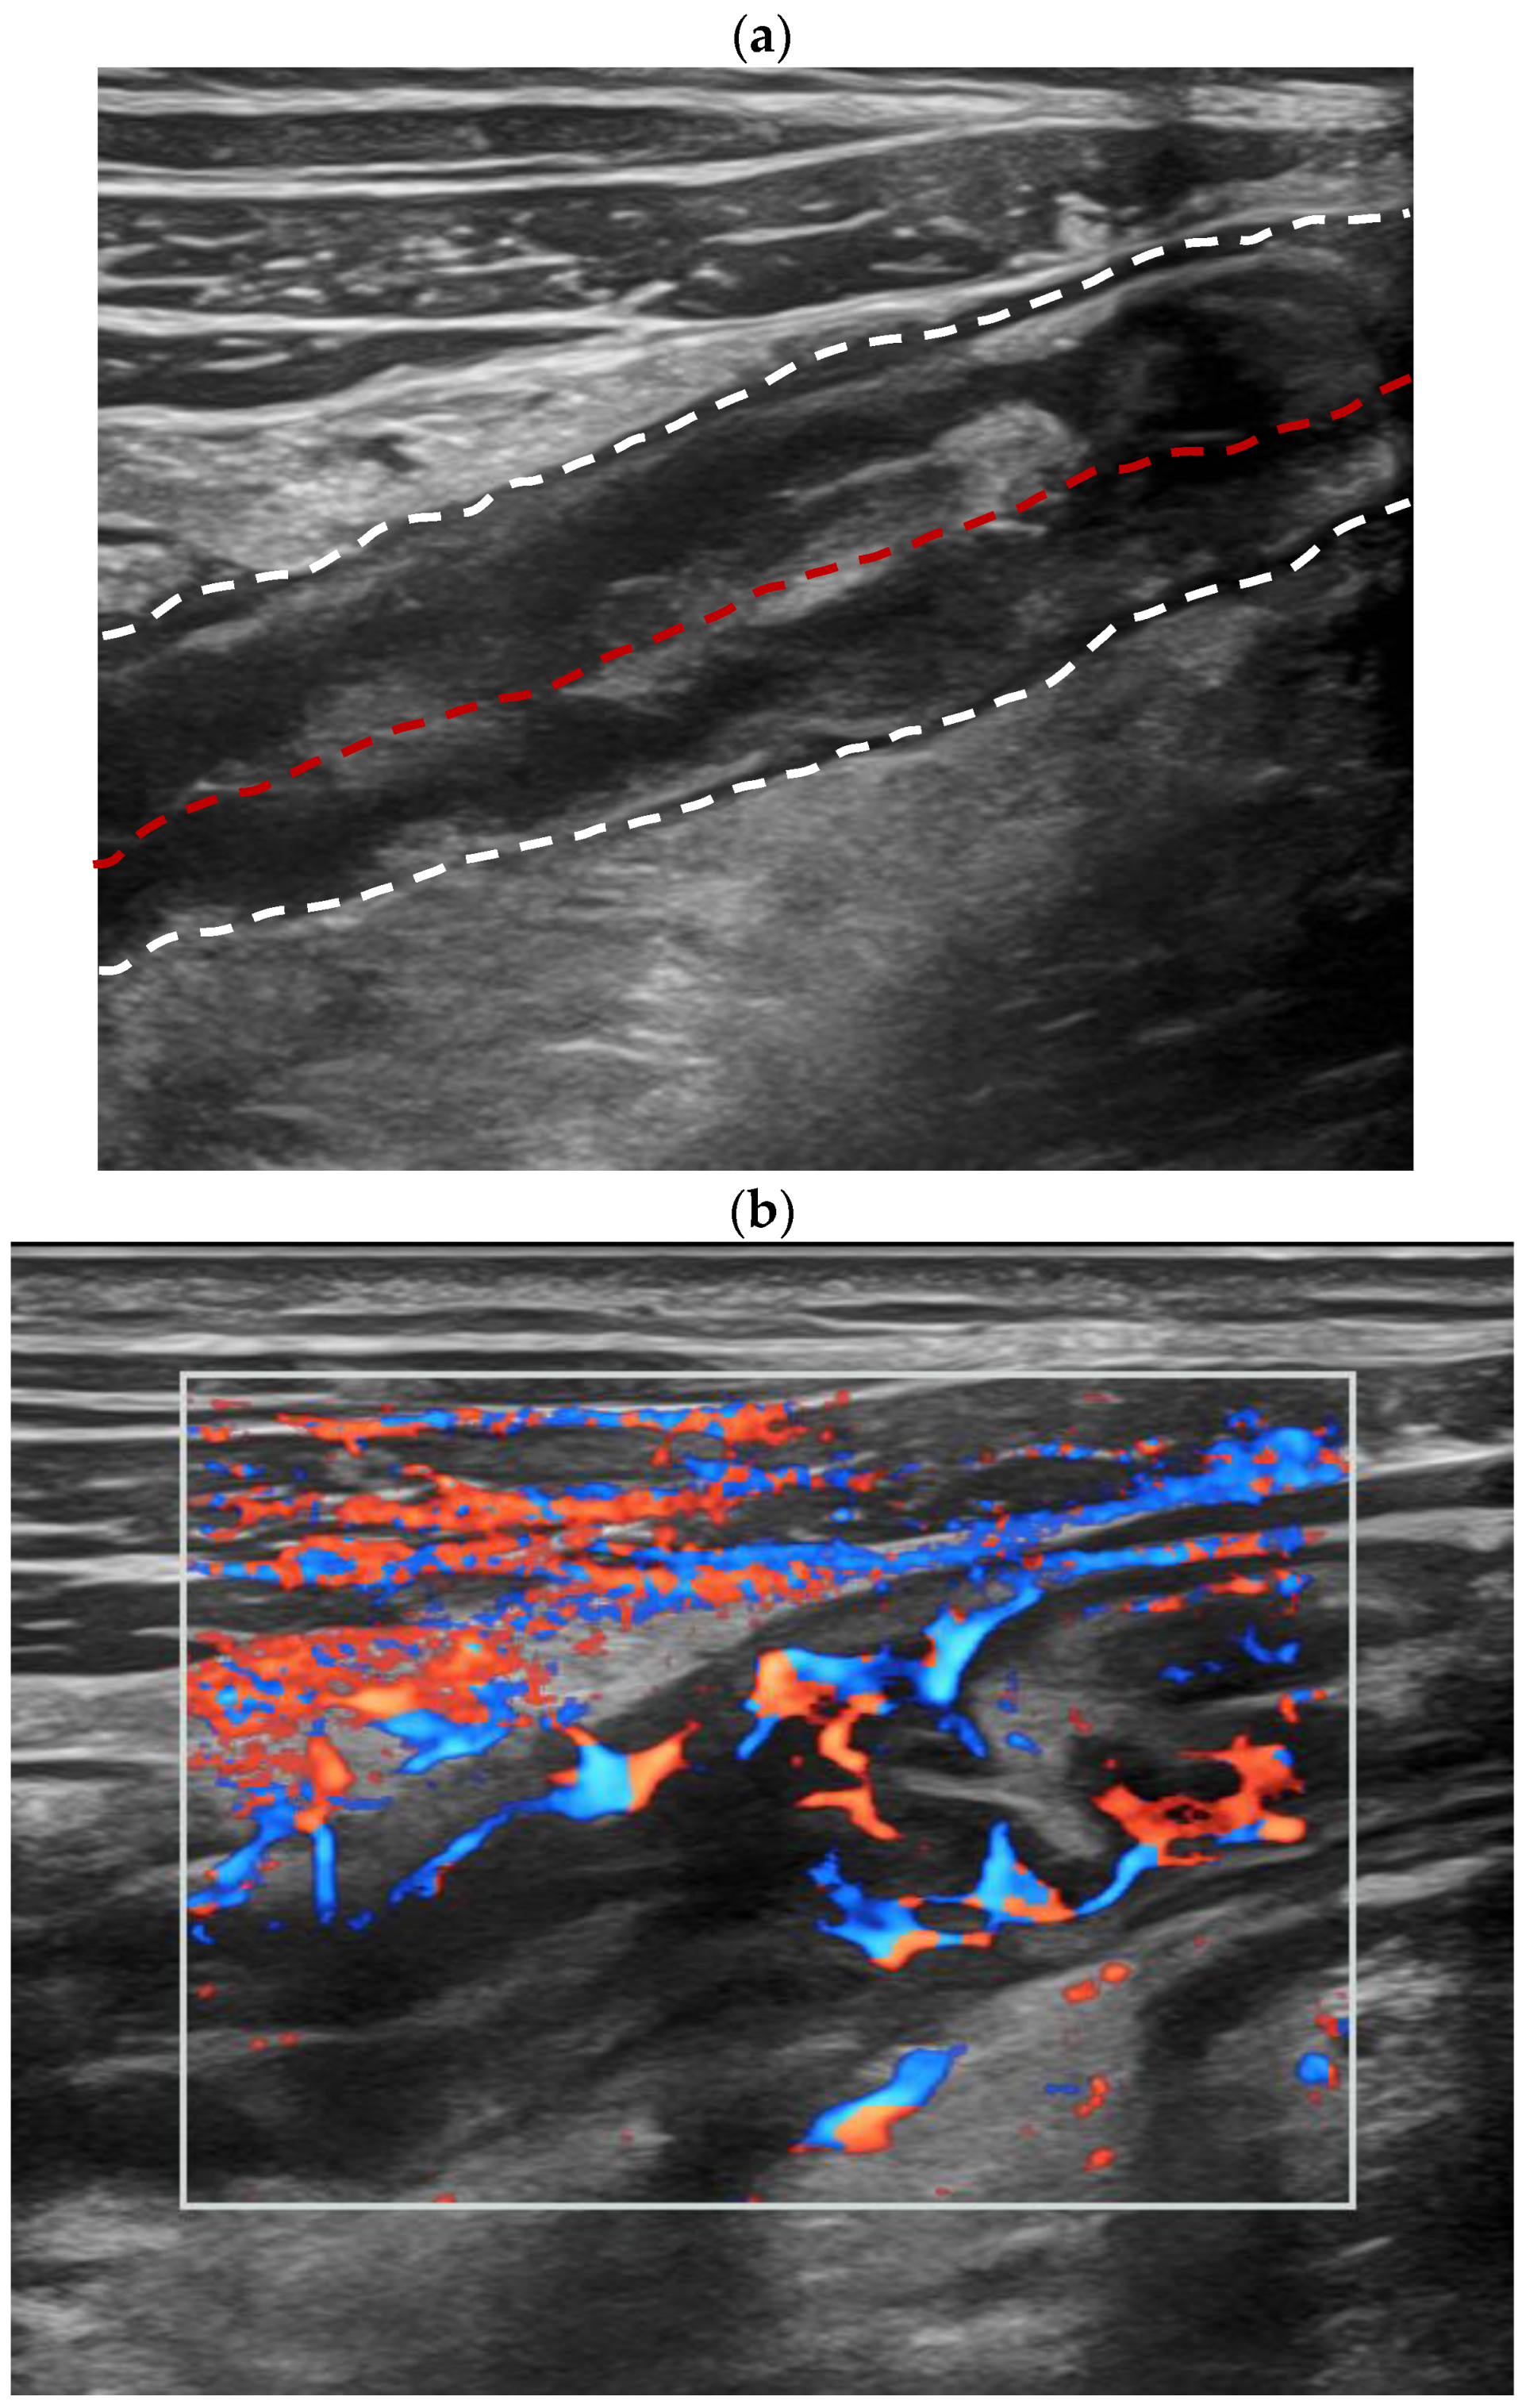

3.3. Dynamic Contrast-Enhanced Ultrasound (DCE-US) Quantitative Analysis

| CEUS enhancement | <0.001 * | ||

| Pattern I | 24 (61.5%) | 1 (7.7%) | |

| Pattern II | 10 (25.6%) | 3 (23.1%) | |

| Pattern III | 5 (12.8%) | 8 (61.5%) | |

| Pattern IV | 0 | 1 (7.7%) | |